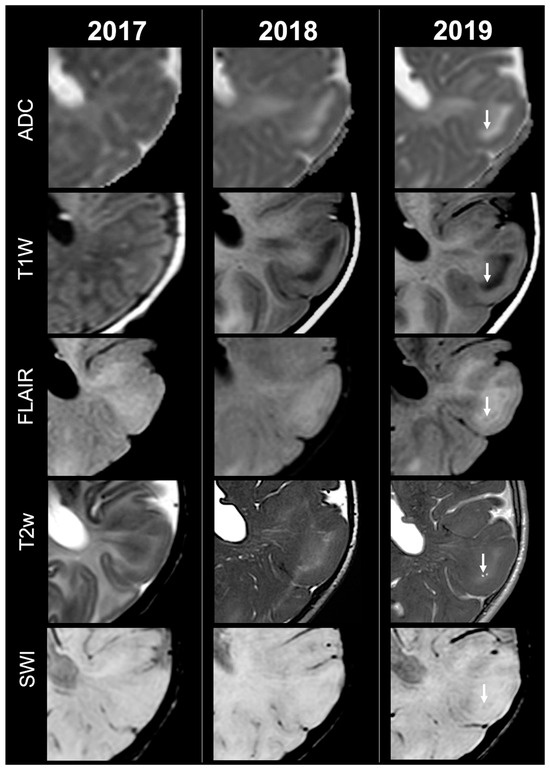

Figure 3.

Left occipital tuber transition from type C1 to C2 at three different timepoints in a female patient diagnosed with TSC1.

Concerning total lesion count, the interobserver agreement was excellent, with an ICC of 0.91 (95% CI: 0.87–0.95). At baseline, the total number of CTs identified across the cohort was 918 (mean ± SD = 16.1 ± 12.4), whereas at the last available MRI follow-up, the overall count increased to 1070 (mean ± SD = 18.8 ± 13.3), corresponding to a net gain of 152 CTs, equal to a relative variation of +17%. When stratified by tuber type, distinct trajectories were observed over time. Type A CTs, which were relatively abundant at diagnosis (N = 303, mean ± SD = 5.3 ± 7.0), decreased to 255 (mean ± SD = 4.5 ± 5.9) at follow-up, yielding a reduction of 48 lesions (−16%). Conversely, type B CTs showed an opposite trend, increasing from 438 (mean ± SD = 7.7 ± 8.4) at baseline to 556 (mean ± SD = 9.8 ± 8.6) at follow-up, corresponding to a net increase of 118 tubers (+27%). An example of MRI signal evolution from tuber A to tuber B is shown in Figure 1. Similarly, type C1 CTs rose from 160 (mean ± SD = 2.8 ± 4.8) to 220 (mean ± SD = 3.9 ± 5.8), with a net gain of 60 tubers (+38%). Type C2 CTs, initially rare at diagnosis (N = 14, mean ± SD = 0.2 ± 0.8), markedly expanded to 33 (mean ± SD = 0.6 ± 1.5), accounting for an increase of 19 CTs (+136%). Finally, type D CTs were only sporadically encountered, with a modest increase from 3 (mean ± SD = 0.1 ± 0.3) to 6 (mean ± SD = 0.1 ± 0.4), equating to a 100% variation. The observed increment of type C2 tubers was attributable almost exclusively to the progressive transformation of pre-existing type B lesions and, more prominently, type C1 lesions, while the increase in type C1 tubers reflected the gradual conversion of both type A and type B CTs that were already detectable at disease onset. An example of MRI signal evolution from tuber B to C1 is shown in Figure 2, while from tuber C1 to C2 in Figure 3. Only in one patient was a type C1 tuber newly identified at follow-up without clear evidence at baseline. In contrast, newly apparent tubers emerging over time but not clearly visible on baseline scans were most frequently represented by type A and type B lesions. Type D tubers were rare overall and were identified in only six lesions from four patients with a particularly high lesion burden; in all but one case they represented the evolution of type A or type B CTs (an example of MRI signal evolution from tuber A to tuber D is shown in Figure 4), while in a single case they were associated with adjacent subtle calcific foci. Overall descriptive data are summarized in Table 1.